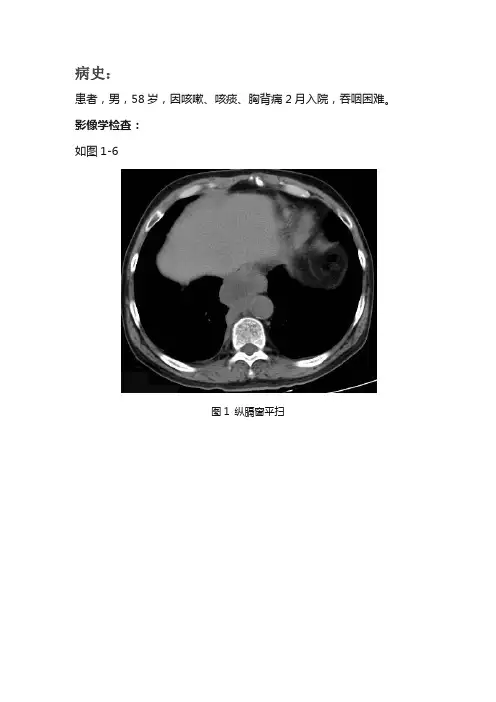

病史:患者,男,58岁,因咳嗽、咳痰、胸背痛2月入院,吞咽困难。

影像学检查:如图1-6图1 纵膈窗平扫图2 纵膈窗动脉期图3 纵膈窗动脉期图4 纵膈窗静脉期图5 纵膈窗静脉期图6 纵膈窗延迟期基础解剖影像:图7图8图9图7-9所示为正常人纵膈窗增强静脉期轴位,显示纵膈内强化血管影、气管、支气管、食管、胸腺、肋骨、肌肉影,可见主动脉弓(黄色箭头)、上腔静脉(蓝色箭头)、肺动脉主干(绿色箭头)、升主动脉(棕色箭头)、左心室(白色箭头)。

诊断及分析:影像描述:胸部CT:胸廓对称,纵膈、气管居中。

后下纵隔可见囊实混合性团块影(蓝色箭头),大小约5.8X4.4cm,边界尚清,中心不规则形囊性,临近胸膜及右侧外侧胸膜局限性结节样增厚(黄色箭头),食管受压向外侧移位(棕色箭头),增强呈中等不均延迟强化,中心囊性区无强化,胸膜结节中等均匀强化。

病灶与临近纵膈组织分界欠清。

影像诊断:后下纵膈囊实混合性占位病变,病变与周围纵膈结构分界欠清,考虑纵膈型肺癌可能。

分析思路:从临床病史、年龄、部位、大小、形态、增强等方面具体分析如下:1、临床病史和年龄:老年男性,提示恶性肿瘤可能,炎症不除外。

年轻人提示炎症及结核。

实验室检查白细胞增高提示炎症。

临床病史高热提示炎症,低热、盗汗提示肺结核。

咳血提示恶性肿瘤、肺结核、支气管扩张。

本例提示吞咽困难,需要注意食管及周围病变病变可能。

2、部位及大小:周围型肺癌位于肺周边。

中心型肺癌位于段以上。

肺结核多位于上叶尖后段及下叶背段。

肺脓肿无特殊。

本例病变累及后下纵膈,食管整体管壁未见增厚,密度均匀,整体受压移位,考虑非食管来源。